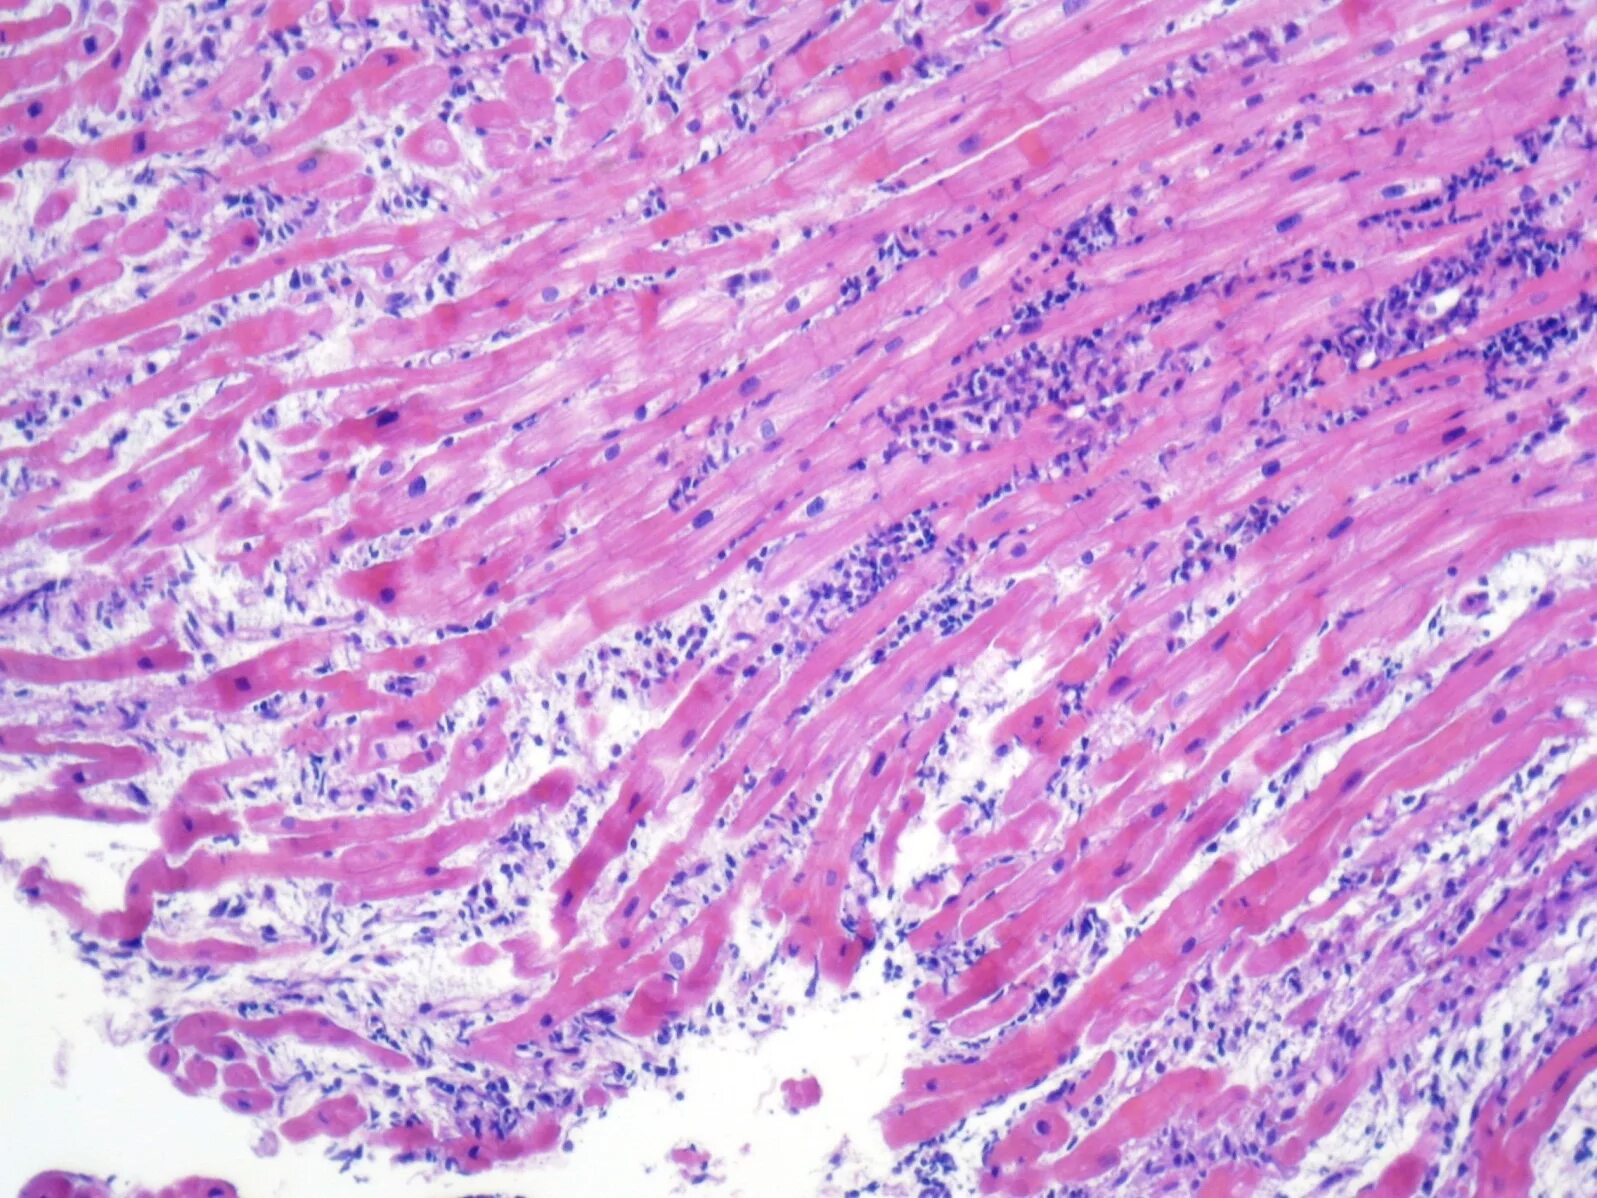

Миокард гистология